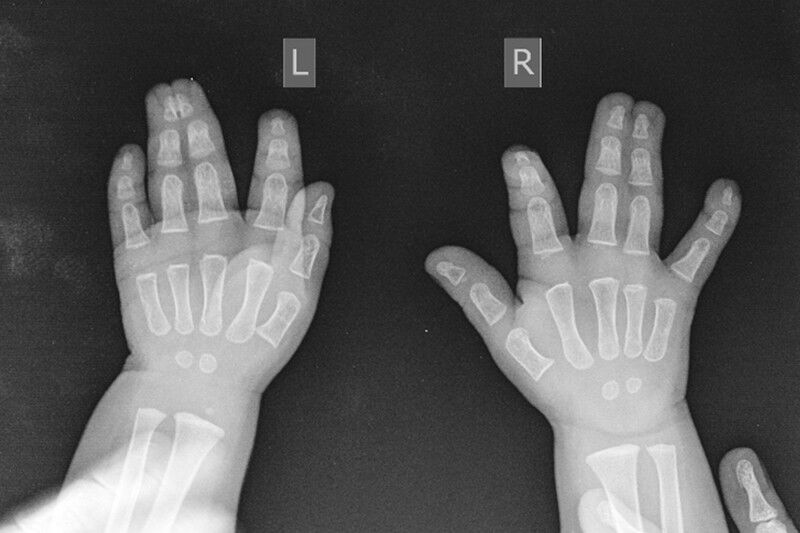

«Полная кожная синдактилия III-IV пальцев правой кисти, кожно-костная синдактилия III-IV пальцев левой кисти», — так звучит поставленный диагноз.

«Методика включает 2 этапа: первый – наложение аппарата Илизарова для создания запаса мягких тканей. Мы начинаем выращивать кожу для формирования межпальцевых промежутков. После этого разделяем пальцы, а появившийся раневой дефект закрываем выращенной кожей. Благодаря данной методике отсутствует необходимость брать кожу с донорских участков», — объясняет суть методики Денис Тягунов, заведующий травматолого-ортопедическим отделением №13 НМИЦ ТО имени акад. Г. А. Илизарова Минздрава России.